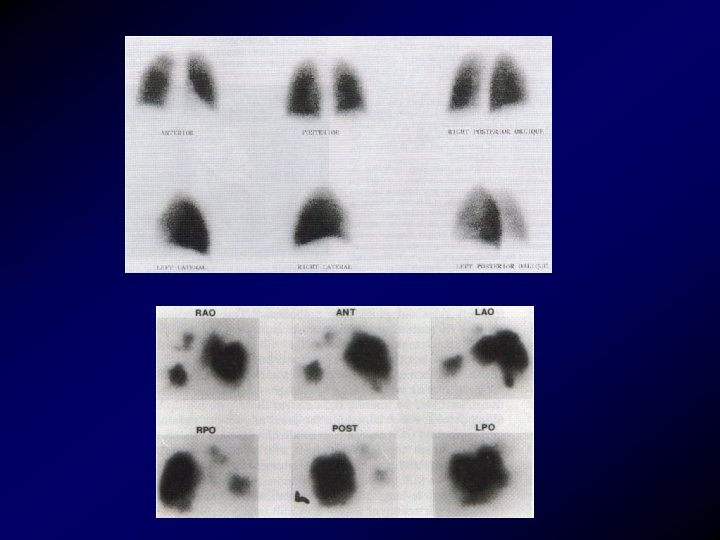

Scintigrafia polmonare • La scintigrafia polmonare ventilatoria e perfusionale, talora di difficile esecuzione la ventilatoria per le condizioni critiche del paziente che non permettono una corretta esecuzione dell'indagine e per le difficoltà tecniche legate all'indagine stessa. Una scintigrafia ad alta probabilità di embolia (difetti di perfusione con ventilazione normale) non necessita di angiografia per la conferma diagnostica. Una scintigrafia normale esclude la diagnosi di embolia. Una scintigrafia a probabilità intermedia o bassa necessità di controllo angiografico.